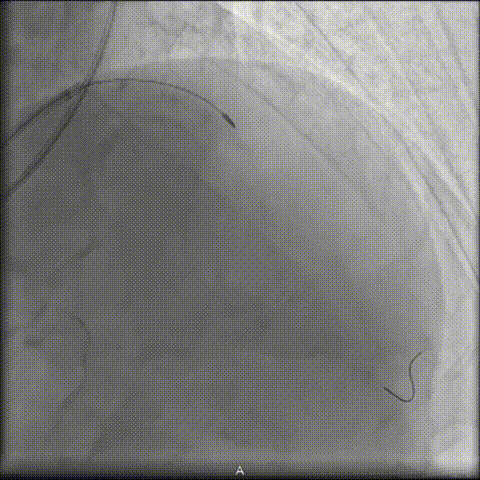

后续NC球囊扩张充分,支架植入顺利。

术后OCT确认支架膨胀充分,贴壁良好。造影提示无残余狭窄,TIMI血流Ⅲ级。